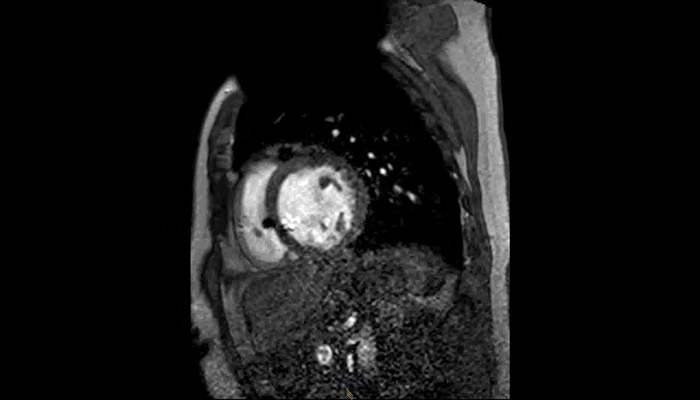

MRI of heart with MR Conditional ICD

A patient with an MR Conditional ICD and suspected myocarditis presented for MRI. This short axis view of the heart is created with an SSFP (steady state free precession) sequence on a Philips Achieva 1.5T system. The cardiac MRI exam reveals normal dimensions and regular function of the right and left ventricle. Note the ICD lead in the right ventricle (arrow) and the signal void in the left pectoral region, indicating the ICD-IPG (asterisk). Courtesy of Dr. Sommer.